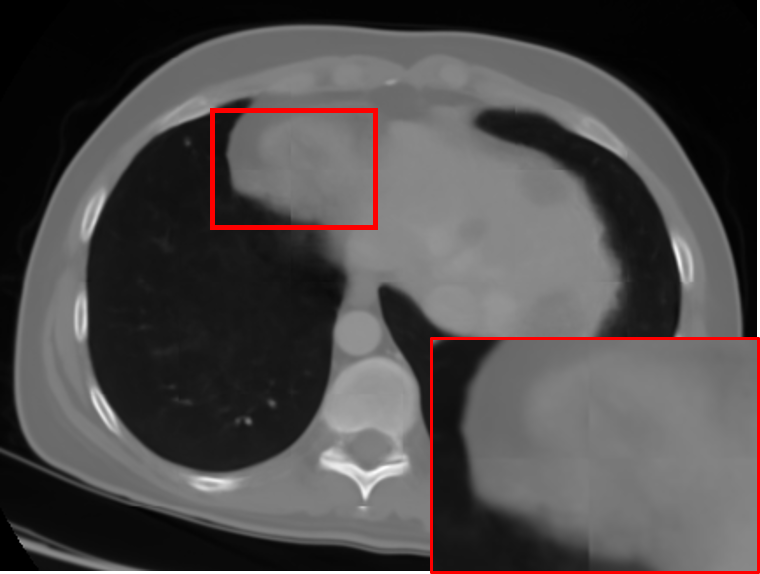

where Igtx=Ix(y,z)subscriptsuperscript𝐼𝑥𝑔𝑡superscript𝐼𝑥𝑦𝑧I^{x}_{gt}=I^{x}(y,z) and Igty=Iy(x,z)subscriptsuperscript𝐼𝑦𝑔𝑡superscript𝐼𝑦𝑥𝑧I^{y}_{gt}=I^{y}(x,z) in the densely-sampled volume I𝐼I. From the axial perspective, Isag(x,y,z)subscript𝐼𝑠𝑎𝑔𝑥𝑦𝑧I_{sag}(x,y,z) and Icor(x,y,z)subscript𝐼𝑐𝑜𝑟𝑥𝑦𝑧I_{cor}(x,y,z) provide line-by-line estimations for the missing axial slices. However, since no constraint is enforced on the estimated axial slices, inconsistent interpolations lead to noticeable artifacts, as shown in Fig. 4. We resolve this problem in the RFN stage of the proposed pipeline.

Refer to caption

(a) Isagz(x,y)superscriptsubscript𝐼𝑠𝑎𝑔𝑧𝑥𝑦I_{sag}^{z}(x,y)

(b) Icorz(x,y)superscriptsubscript𝐼𝑐𝑜𝑟𝑧𝑥𝑦I_{cor}^{z}(x,y)

(c) Iavgz(x,y)superscriptsubscript𝐼𝑎𝑣𝑔𝑧𝑥𝑦I_{avg}^{z}(x,y)

(d) Ifuse(x,y)subscript𝐼𝑓𝑢𝑠𝑒𝑥𝑦I_{fuse}(x,y)

Figure 4: (a) The axial slice generated from Isagsubscript𝐼𝑠𝑎𝑔I_{sag}. (b) The axial slice generated from Icorsubscript𝐼𝑐𝑜𝑟I_{cor}. Some details are better resolved by (a) and others by (b). Both of them exhibit directional artifact due to a lack of constraints in the (x,y) plane. This is resolved through RFN in (d), which refines their average Iavgsubscript𝐼𝑎𝑣𝑔I_{avg}, as shown in (c)